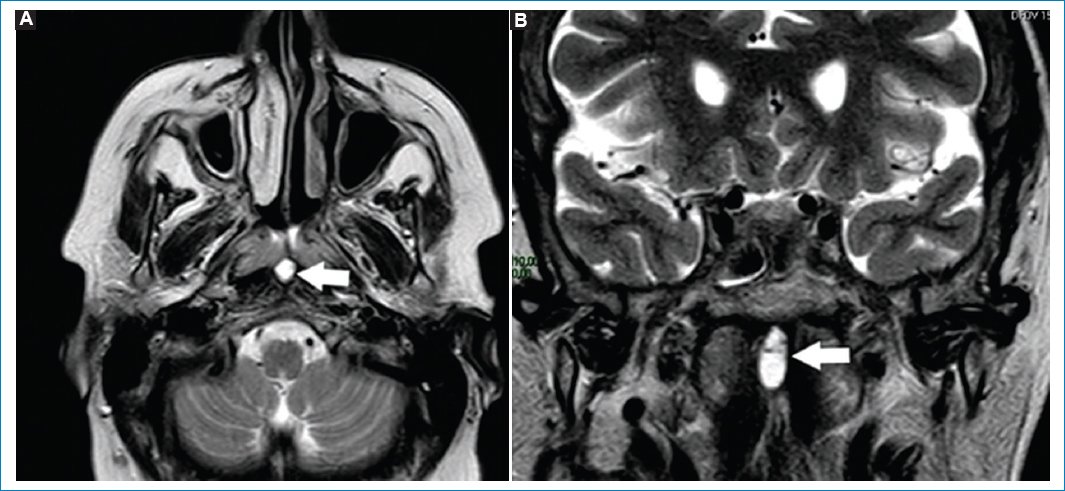

La efusión del ápex es acúmulo del líquido estéril, sin asociarse a síntomas clínicos. Las cavidades mastoideas presentan continuidad con el ápex petroso, por lo que pueden drenar su contenido en un ápex neumatizado29. Se objetiva hipointenso en T1 e hiperintenso en FLAIR y T2, sin realzar con gadolinio (Fig. 9)29.

Figura 9. Imágenes potenciadas en T2. Cortes: axial (A) y coronal (B). Se observa (flechas) colección en el ápex izquierdo. Esta es hiperintensa en T2, resaltando en comparación del ápex neumatizado contralateral.

La presencia de hiperintensidades en las celdillas mastoideas, valoradas en secuencias ponderadas en T2, suele denominarse mastoiditis (Fig. 10)30. Este es un hallazgo fortuito, cuando la RM se pide por otro motivo; incluso algunos estudios de cohorte sugieren no mencionar la palabra mastoiditis, reemplazándola en el informe por ocupación de cavidades mastoideas. Cuando se encuentre la presencia de hiperintensidades en las cavidades mastoideas, deberá correlacionarse con la clínica, antes de denominarse mastoiditis30.

Figura 10. Corte axial (A) y sagital (B), potenciados en T2. Ocupación de cavidades mastoideas izquierdas (flechas), valoradas como hiperintensidades puntiformes y asimétricas.

Habitualmente la hiperintensidad se debe a acumulación de líquido estéril, por disfunción tubárica30.